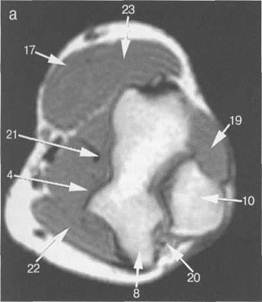

Рис. 19.33. МРТ локтевого сустава. Аксиальная плоскость.

а: 4 — m. brachialis; 8 — медиальный надмыщелок; 10 — лок­тевой отросток локтевой кости; 17 — m. brachioradialis; 19 — т. anconeus; 20 — nervusulnaris; 21 — сухожи­лие т. biceps brachii; 22 — т. pronator teres.

б: 1 — головка лучевой кости; 2 — локтевая кость; 3 — п. medianus; 4 — arteria, vena, п. radialis; 17 — m. brachioradialis; 21 — сухожилие m. biceps brachii; 22 — m. pronator teres.